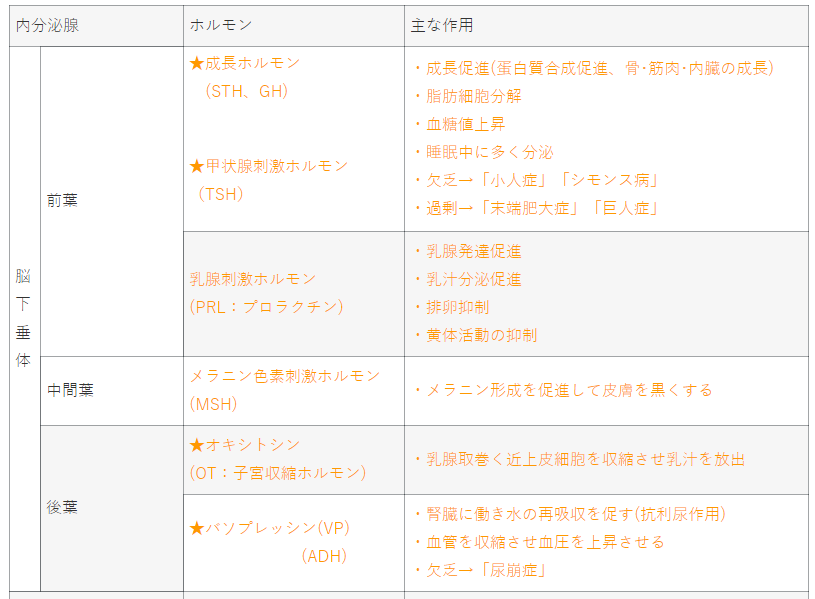

内分泌腺とホルモンの主な作用

(77pm46、76am62、75pm61、74am55pm62、73am53、72am52、71am61pm59、70am60.pm56、69am55.56、68am50.am62.pm61、65.11、64.13、63.20、60.11.14)

| 内分泌腺 | ホルモン | 主な作用 | ||

| 脳 下 垂 体 |

前葉 | ★成長ホルモン (STH、GH) ★甲状腺刺激ホルモン |

・成長促進(蛋白質合成促進、骨・筋肉・内臓の成長) ・脂肪細胞分解 ・血糖値上昇 ・睡眠中に多く分泌 ・欠乏→「小人症」「シモンス病」 ・過剰→「末端肥大症」「巨人症」 |

|

| 乳腺刺激ホルモン (PRL:プロラクチン) |

・乳腺発達促進 ・乳汁分泌促進 ・排卵抑制 ・黄体活動の抑制 |

|||

| 中間葉 | メラニン色素刺激ホルモン (MSH) |

・メラニン形成を促進して皮膚を黒くする | ||

| 後葉 | ★オキシトシン (OT:子宮収縮ホルモン) |

・乳腺取巻く近上皮細胞を収縮させ乳汁を放出 | ||

| ★バソプレッシン(VP) (ADH) |

・腎臓に働き水の再吸収を促す(抗利尿作用) ・血管を収縮させ血圧を上昇させる ・欠乏→「尿崩症」 |

|||

| 間脳 視床下部 |

・成長ホルモン抑制ホルモン (ソマトスタチン) ・プロラクチン放出ホルモン (PRH) ・プロラクチン抑制ホルモン (ドーパミン) |

・脳下垂体前葉からのホルモン放出を 促進あるいは抑制する ・TRHはプロラクチン放出作用をもつ |

||

| 松果体 | メラトニン | ・黒色色素胞を収縮させる ・概日リズムに関連 ・生殖腺の発達及び活動を抑える |

||

| 甲状腺 | ★サイロキシン (T4) ★トリヨードサイロニン |

・神経の発達と機能維持 ・血糖値上昇促進 ・体熱産生促進 ・蛋白質、脂肪、炭水化物の代謝促進 ・過剰→「バセドウ病」 ・欠乏→「クレチン病」「粘液水腫」 |

||

| ★カルシトニン(CT) | ・骨の形成促進、 尿細管でのCaの分泌促進または抑制 ・Pの代謝に関連 |

|||

| 副甲状腺 | ★パラソルモン(PTH) | ・骨のCaを血中に遊離 ・尿細管でのCaの再吸収を促進 ・Pの代謝に関連 ・血中Caの増加 ・過剰→「骨軟化症」「くる病」 ・欠乏→「テタニー症」 |

||

| 副 腎 |

★ 皮 質 |

束状帯 | 糖質コルチコイド ★ 代表:コルチゾール |

・肝臓に貯蔵されているグリコーゲンを グルコースに分解促進 ・抗炎症・抗アレルギー作用 ・ストレスに反応 ・過剰→「クッシング症候群」 |

| 球状帯 | 電解質コルチゾイド 代表:アルドステロン |

・尿細管でのNa+・水分の再吸収、 K+排泄促進 ・血圧調節 ・過剰→「アルドステロン病」 |

||

| 網状帯 | ★性ホルモン 代表:アンドロゲン |

・思春期男性の第2次性徴 ・欠乏→「アジソン病」 |

||

| ★髄質 | カテコールアミン (アドレナリン、 ノルアドレナリン) |

・ともに、交感神経活動に類似の作用 ・アドレナリン :全身的な作用を強く引き起こす ・ノルアドレナリン :末梢血管に特に強く作用して 血圧を上昇させる ・褐色細胞腫では、副腎髄質ホルモン過剰となる |

||

| 膵臓 | α細胞 | ★グルカゴン | ・肝臓に貯蔵されているグリコーゲンの分解促進 | |

| β細胞 | ★インスリン | ・グリコーゲンの合成促進 ・細胞の糖取り込み(糖の消費)を促進 ・過剰→「低血糖症」 ・欠乏→「糖尿病」 |

||

| δ細胞 | ★ソマトスタチン | ・グルカゴン、インスリンの分泌抑制 | ||

| 生 殖 腺 |

卵 巣 |

卵胞 | エストロゲン | ・女性第2次性徴の発現・成熟を促進 ・排卵誘発 ・子宮粘膜の周期的増殖 ・乳腺の発育促進 |

| 黄体 | プロゲステロン | ・子宮粘膜の線分泌を高める ・排卵の抑制 ・乳腺の発育促進 ・妊娠の維持 |

||

| ★精巣 | アンドロゲン テストステロン |

・男性第2次性徴の発現・成熟を促進 ・精子形成促進 ・男性生殖器の発育促進 ・体組織蛋白の合成促 |

||

| 内 分 泌 で な い 器 官 |

胎盤 | ヒト絨毛性性腺刺激ホルモン (hCG) |

・妊娠すると尿への性腺刺激ホルモンの 排泄が著しく増加 |

|

| ★傍糸球体細胞 (腎臓) |

レニン | ・血圧低下時に血管を収縮させ、 循環血液量を増やし、血圧を上昇させる |

||

| ★腎臓 | エリスロポエチン (EPO) |

・赤血球の生成を促進 → 機能低下で貧血になる |

||

| 心臓 | 心房性ナトリウム 利尿ペプチド |

・Na+の排泄を促進 | ||

| 消 化 管 腺 |

十二指腸 粘膜 |

セクレチン | ・膵液の放出を促進 ・ペプシンの分泌促進 |

|

| コレシストキニン パンクレオザイミン |

・膵液消化酵素の分泌促進 ・胆嚢収縮 ・オッディの括約筋弛緩 |

|||

| ★胃(幽門部) | ガストリン | ・塩酸、ペプシノーゲンの分泌促進 | ||

| 耳下腺 | パロチン | ・骨の成長、蛋白代謝、血糖低下に影響を及ぼす | ||